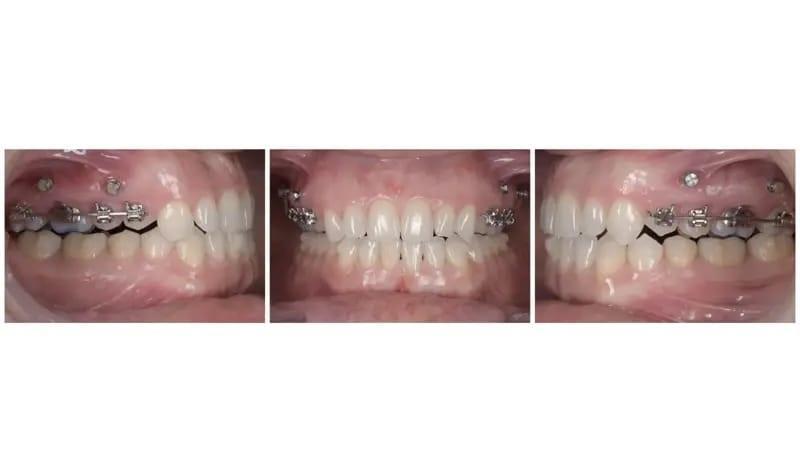

После этапа восстановления, который включал в себя использование 12 пар элайнеров, лечение было продолжено с акцентом на дальнейшее проникновение в заднюю часть верхней челюсти для точной настройки вертикальной коррекции (фото 9). Вторая серия элайнеров была нацелена на окончание лечения с конкретными целями улучшения задней интеркуспации, достижения точной коррекции средней линии и улучшения сагиттальных взаимоотношений с помощью задней IPR и билатеральное использование эластиков III класса (фото 10).

Фото 9a–d: Ситуация после установки 20-й пары элайнеров (FACE reset).